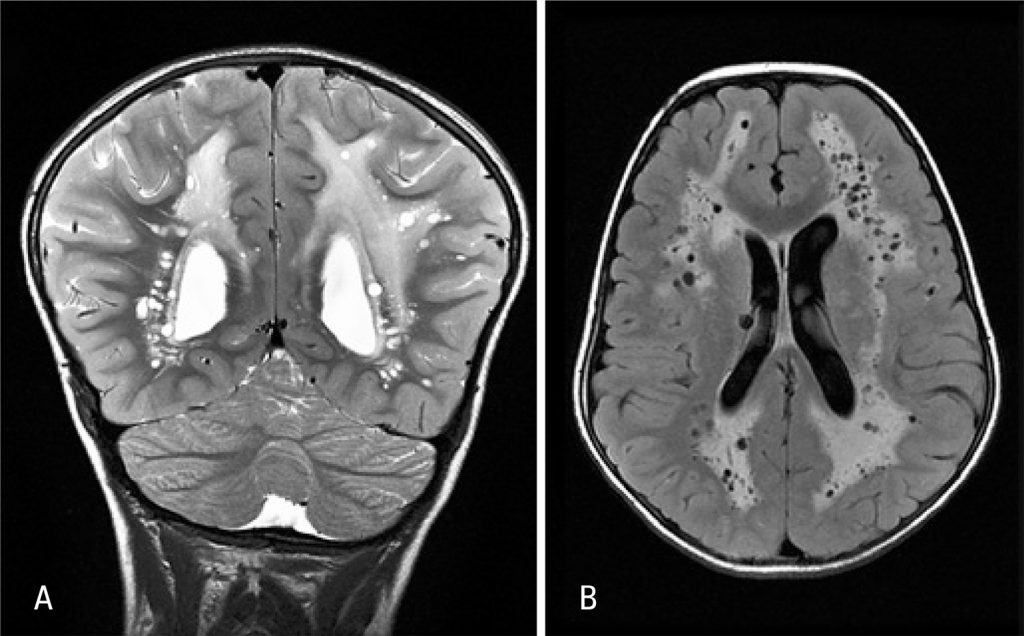

Criança de 7 anos, do gênero masculino, previamente saudável, recorreu ao serviço urgência por cefaleia occipital e despertar noturno com 1 semana de evolução. Apresentava manchas hipopigmentadas lineares segundo as linhas de Blaschko no hemitórax e membro superior esquerdos (); macrocrânia, fenda palpebral antimongoloide, alteração do contorno pupilar no olho esquerdo e sindactilia. Sem alterações no exame neurológico. A tomografia computorizada craniencefálica revelou acentuação da hipodensidade da substância branca e diminutas imagens quísticas. A ressonância encefálica evidenciou extenso processo de leucoencefalopatia e dilatações múltiplas de espaços perivasculares, achados raramente descritos no contexto clínico de hipomelanose de Ito (HI) ().